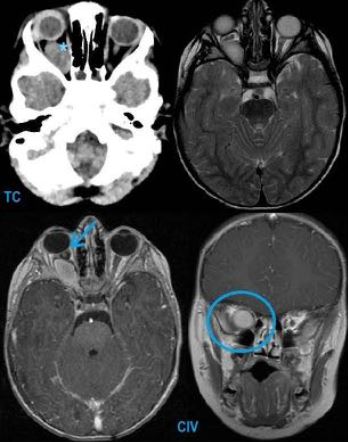

Neoplasias más frecuentes en edad pediátrica diagnosticadas en urgencias

Johanna Marcela Vasquez Veloza, Monica Rebollo Polo, Lucia Riaza Martin, Maria Navallas Irujo, Emili Inarejos Clemente